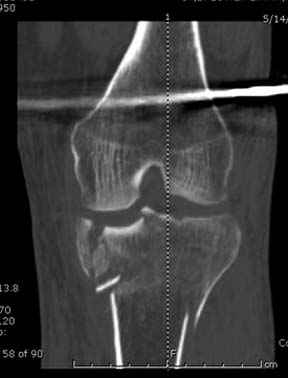

Отдельные переломы тибиал плато и перелом проксимальной трети большеберцовой кости отличаются от переломов тибиал плато с вовлечением диафиза. Здесь перелом тибиал плато типа Schatzker VI, полученный в результате высокоэнергетической травмы. Перелом метафиза образовал отрыв суставной поверхности от диафиза с вовлечением медиального и латерального мыщелков. Двухмыщелковые переломы из-за укрочения опасны развитием компартаментального синдрома, повреждением латерального мениска и связок.

Ваша упорство с минимальными данными защищаться забавляет, и пока не все убедились в Вашей правоте. Для нормальной защиты необходимы аргументированные доказательства исследованиями. КТ сканы и прицельно сделанные снимки коленного сустава, а так все аргументы - не более чем "моя фиксация, мне нравится". Без этих доказательств пока только Ваше упорство.....